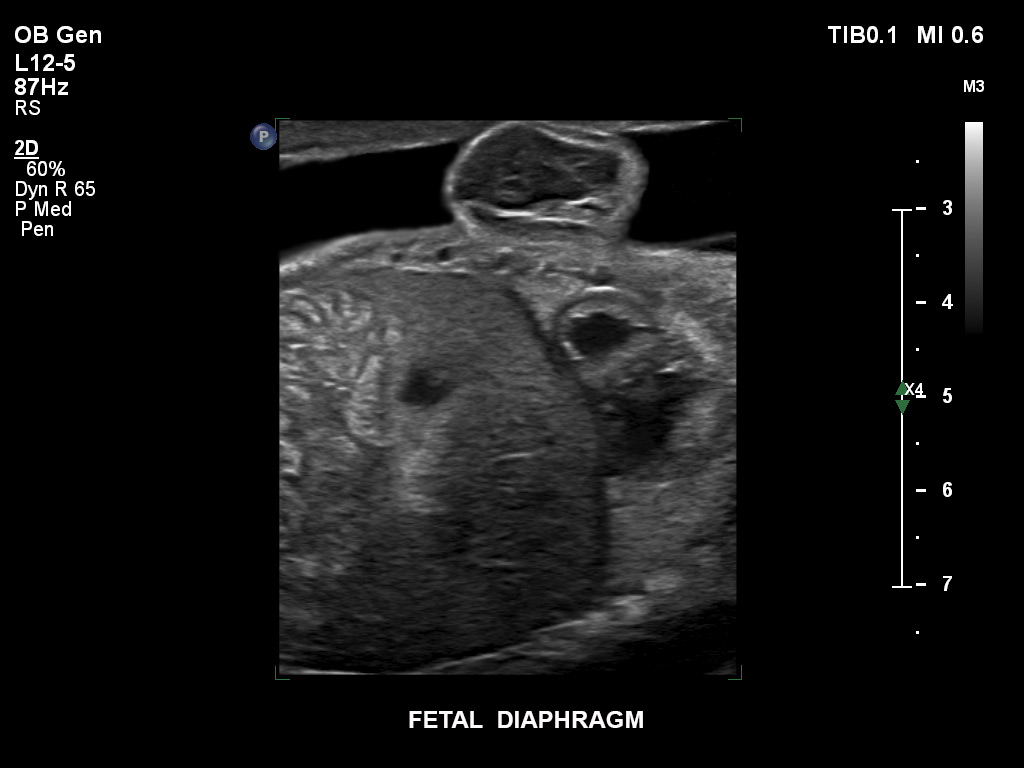

• C9-2 PureWave-Breitband-Convex-Schallkopf für Hochfrequenz-Bildgebung in der Gynäkologie und der Geburtshilfe, insbesondere für die Untersuchung im Hinblick auf mögliche Anomalien im ersten Schwangerschaftstrimester